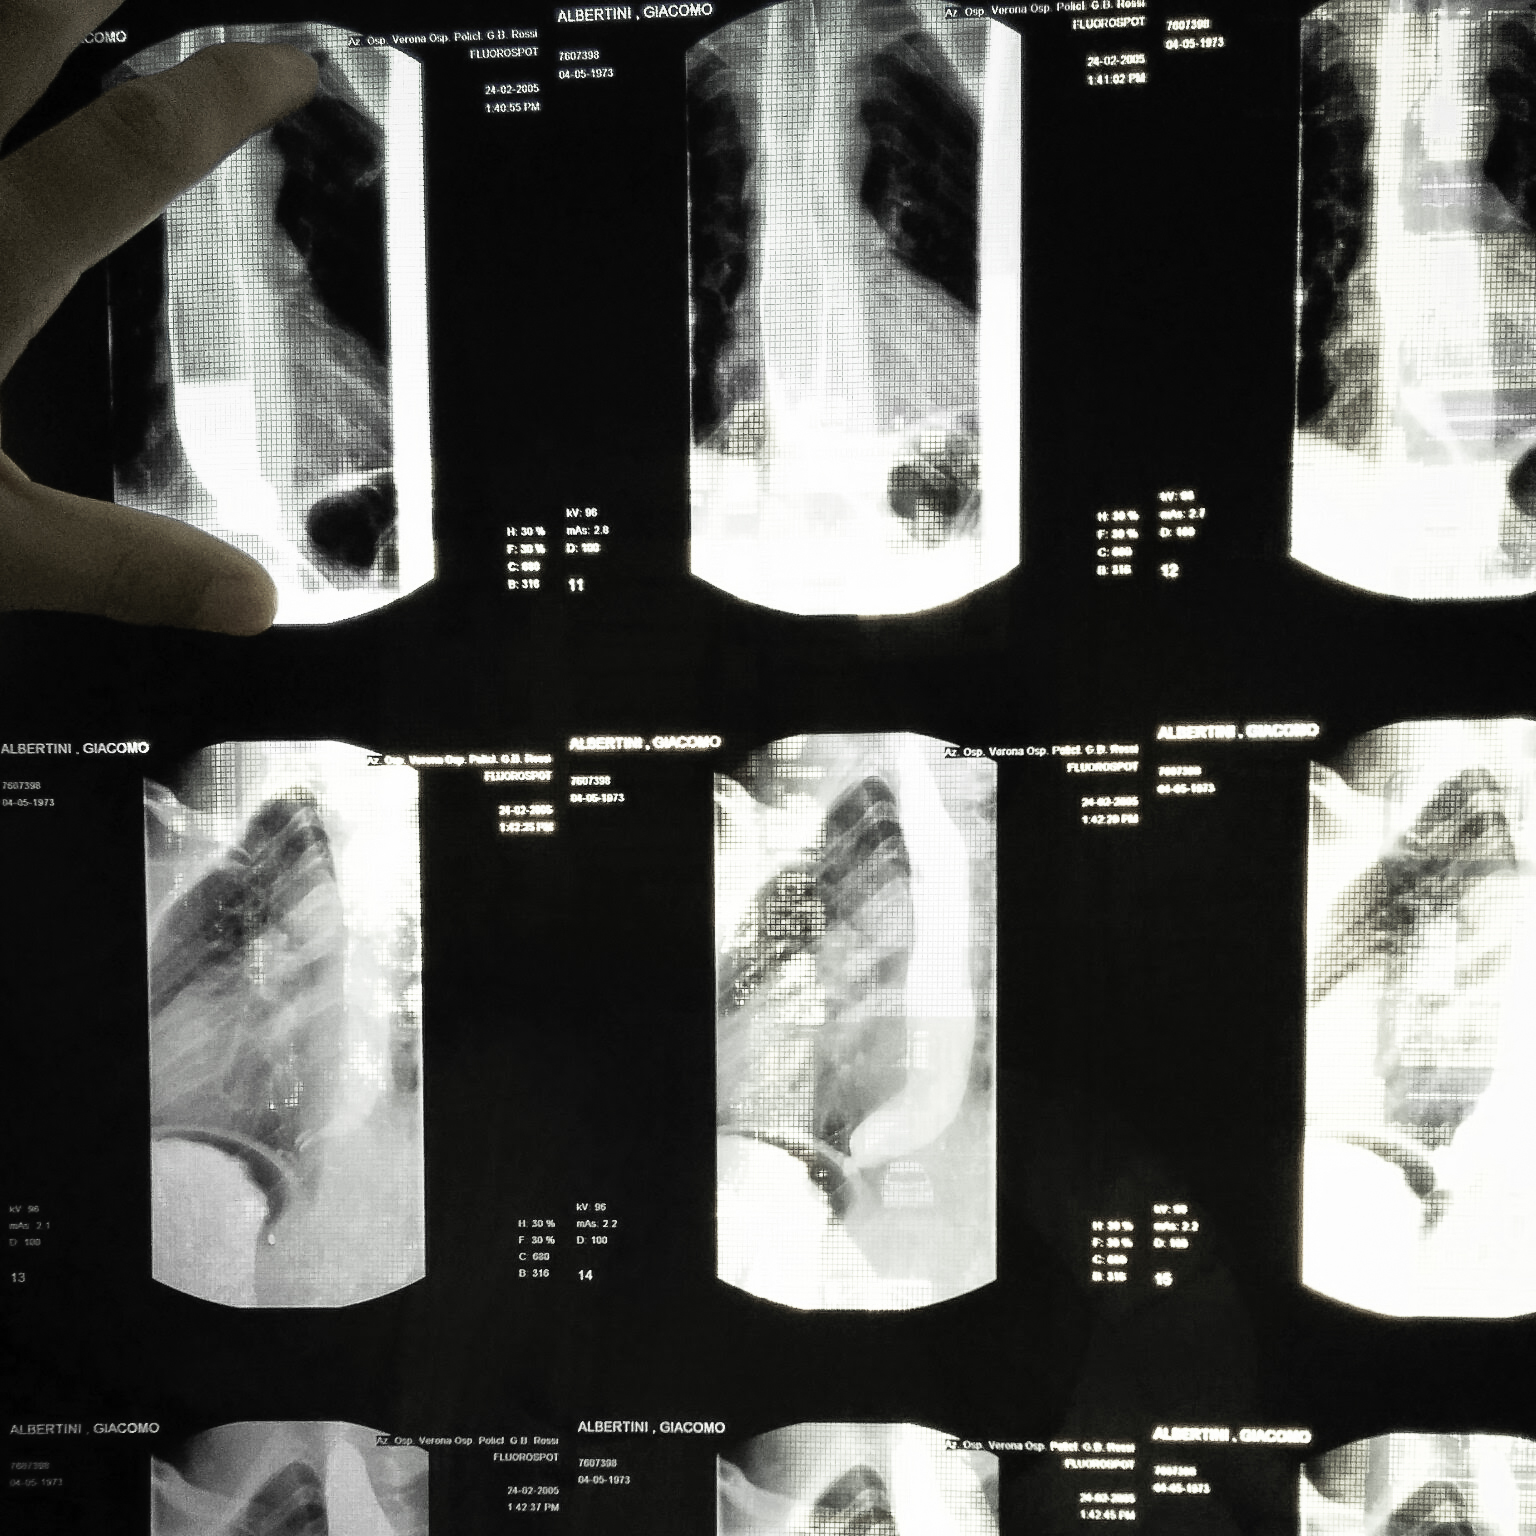

L'Acalasia Esofagea è una malattia rara che annulla la motilità esofagea e colpisce una persona ogni 100.000. La diagnosi tempestiva è molto importante perché progressivamente, oltre alla salute, si annulla la qualità della vita e il benessere psicologico dei malati. Tra i sintomi diretti ci sono infatti la difficoltà di bere semplicemente un bicchier d'acqua, il sentirsi soffocare mangiando, vomito, forti dolori al torace, rigurgito di cibo, serie difficoltà nel riposo notturno. La vita lavorativa e sociale (come andare al ristorante con gli amici) diventa difficile da sopportare provocando un progressivo isolamento dei malati. Proprio perché rara questa malattia è difficile da diagnosticare e a causa dei suoi sintomi aspecifici, spesso occorrono anni per giungere alla diagnosi certa.